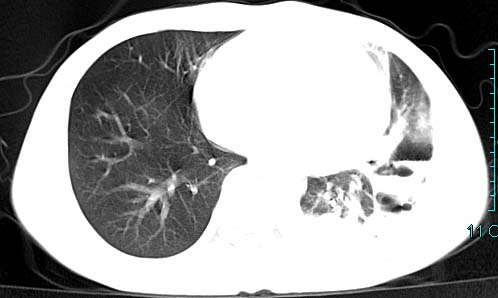

以下是引用qian在2006-3-28 14:32:00的发言:[br]左肺下叶大片状阴影,密度不均,见有条片影和空洞及气液平,少量胸腔积液伴有胸膜增厚,从图像看积液密度比水的密度高,结合病史,考虑左下肺化脓性炎症伴有脓胸。

以下是引用wawaquan在2006-3-28 22:25:00的发言:[br]左上肺舌段多发斑片影。结合“男24y咳嗽咳痰气促伴高热(38.5--39.5)20多天”及穿刺史,[br]考虑1 左下肺化脓性炎症;2脓胸。

以下是引用乡医在2006-3-28 18:37:00的发言:[br]左侧多发液气平面结合患者男24y咳嗽咳痰气促伴高热(38.5--39.5)20多天,查胸水:ldh239.3,总蛋白59.19,tb-ab阴性,利凡它试验+,红c2.7*109,白c1.08*109,分类淋巴92%分叶8%,考虑1脓胸2肺隔离征感染